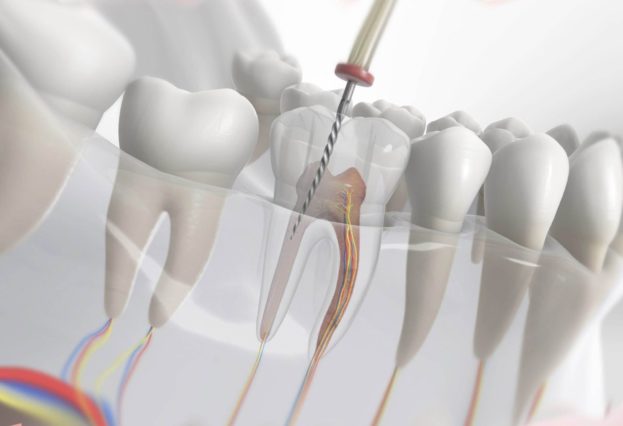

Сложные случаи в эндодонтии: как выбор материала решает исход лечения

В эндодонтии сложные ситуации случаются чаще, чем принято думать. Для врача это не исключение, а рабочая рутина, где каждое движение и каждое решение имеет вес. Суженный канал, выраженные изгибы, необычная конфигурация корневой системы или перфорация способны значительно осложнить лечение. В таких ситуациях итог зависит от того, насколько точно выбран материал и подходит ли он для работы в конкретных условиях. Ошибка на любом этапе легко обнуляет весь проделанный труд.

При лечении зубов с узкими каналами главная задача — не потерять проходимость и удалить инфекцию полностью. Инструменты работают на пределе, поэтому их действие необходимо дополнять химической обработкой. Ирригационные растворы проникают туда, куда не дотянется файл, разрушают микробные отложения и вымывают остатки тканей. На практике для этого берут гипохлорит натрия подходящей концентрации и ЭДТА, которое открывает устья дентинных канальцев и облегчает дальнейшую обтурацию.

Кривизна канала: адаптация и контроль

При выраженной кривизне канала повышается риск образования уступов, перфораций или недообработки апикальной трети. Здесь важна работа не только инструментами, но и препаратами, которые помогут контролировать процесс. Растворы должны обладать хорошей текучестью, чтобы достигать изгибов, а обтурационные материалы — равномерно заполнять даже сложную геометрию канала. Гуттаперчевые штифты с оптимальной конусностью и герметики с низкой усадкой обеспечивают плотное прилегание без пустот.